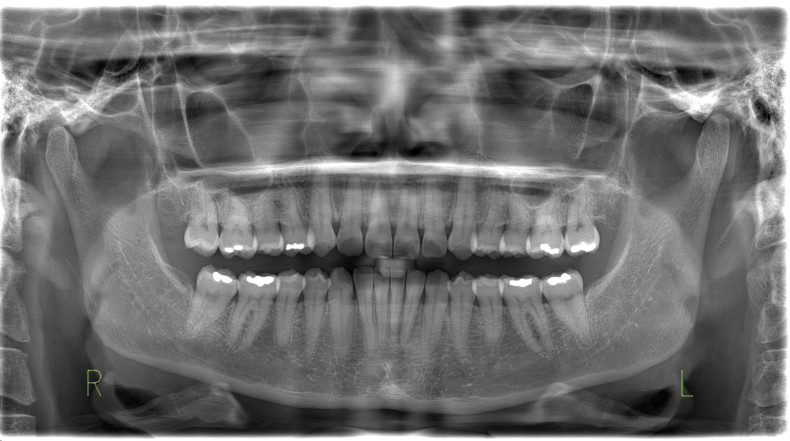

Die FRS-Auswertung (Abb. 1d) ergab eine distal-basale Kieferrelation nach WITS (2,6 mm) bei tendenzieller maxillärer Prognathie (SNA 86,5°). Aus der dentalen Analyse des FRS ging eine deutliche Anteinklination der Oberkieferinzisivi (IOK-NL 126,5°) und eine manifeste Anteinklination der Unterkieferinzisivi (IUK-ML 103,6°) bei stark verkleinertem Interinzisalwinkel (IOK-IUK 112,3°) hervor. Die vertikalen Parameter ergaben einen brachiofazialen Gesichtsschädelaufbau. Die Auswertung des OPG (Abb. 1e) zeigte eine adulte Dentition mit fehlenden dritten Molaren. Außerdem war eine extreme Mesialkrümmung der Wurzel 25 erkennbar. Es zeigte sich ein moderater generalisierter horizontaler Knochenabbau des Limbus alveolaris im Ober- und Unterkiefer von ca. 15 Prozent.